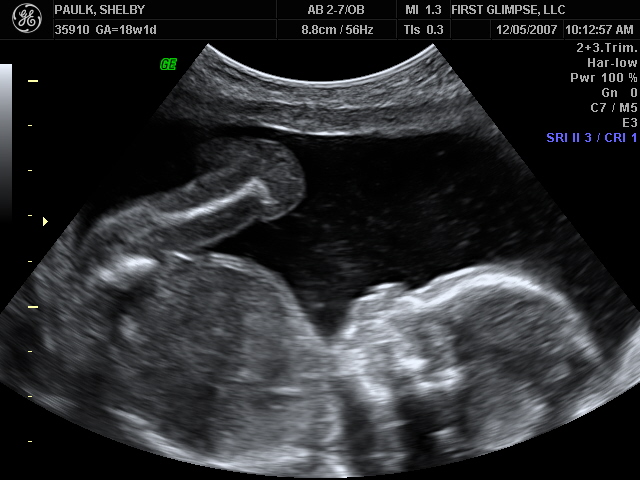

We had the ultrasound for baby number #2 on Tuesday, as we like to refer to HIM as (at least until we come up with a name, which could be a while given our track record). Yes, I said HIM…we are having a baby BOY!! We are so blessed to be have one of each. God is so good. Here are a few of the many ultrasound pictures that were taken. God has blessed us with one very healthy baby and we pray that this little guy is just as healthy. So far the docs. say everything looks great, we’ll have another ultrasound around 28 weeks because of where the placenta is located right now. It needs to move because it is blocking the cervix, but the ultrasound tech said that 9 of 1o times it will move…we pray that it does, because if it doesn’t I will have to have a C-Section.